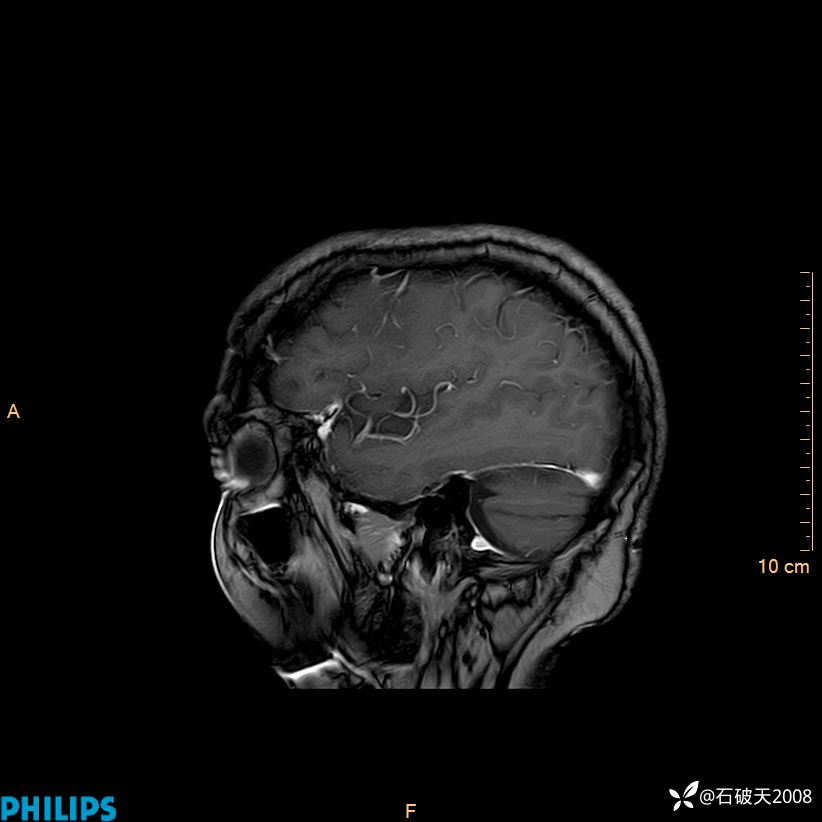

增强矢状位

增强冠状位